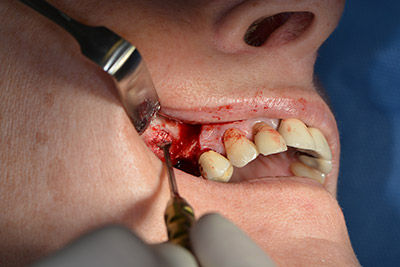

En el siguiente paso se efectúa la elevación del suelo del seno maxilar, a la vez que se coloca el implante. Para la fenestración lateral de la pared del seno maxilar Implantmed también cuenta con un ajuste predefinido en la primera posición.

La ventana se crea a una velocidad de 35.000 rpm y, a continuación, la membrana de Schneider se prepara en sentido craneal (figuras 13 a 14).

Acto seguido, se coloca el implante y se estructura el hueso. Dado el tamaño del aumento, en el caso que nos ocupa se utilizó hueso autógeno, que había surgido como virutas de fresado en el implante 16 y en la fenestración 14 y se había recogido con un colector óseo, y se combinó con material de reemplazo óseo.

Una membrana reabsorbible formó la barrera en sentido bucal y cubrió el aumento. Por último se procedió a la sutura de modo que no penetrara saliva (figuras 15 a 19).